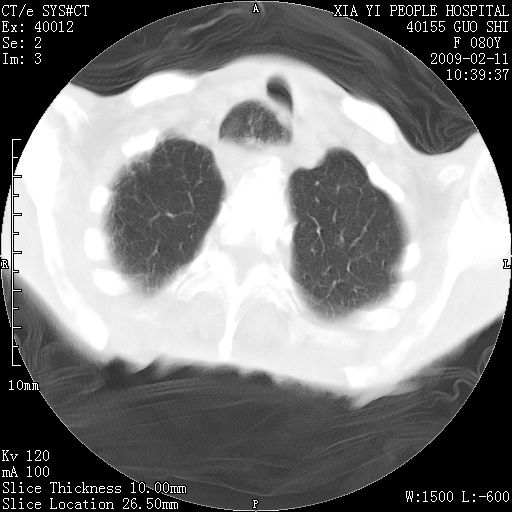

以下是引用随光逐影在2009-2-16 16:34:00的发言:[br]1)考虑右前纵隔皮样囊肿。2)双侧少量胸腔积液。

以下是引用zjzjr在2009-2-16 17:30:00的发言:[br]支持囊性畸胎瘤 双侧少量胸腔积液。